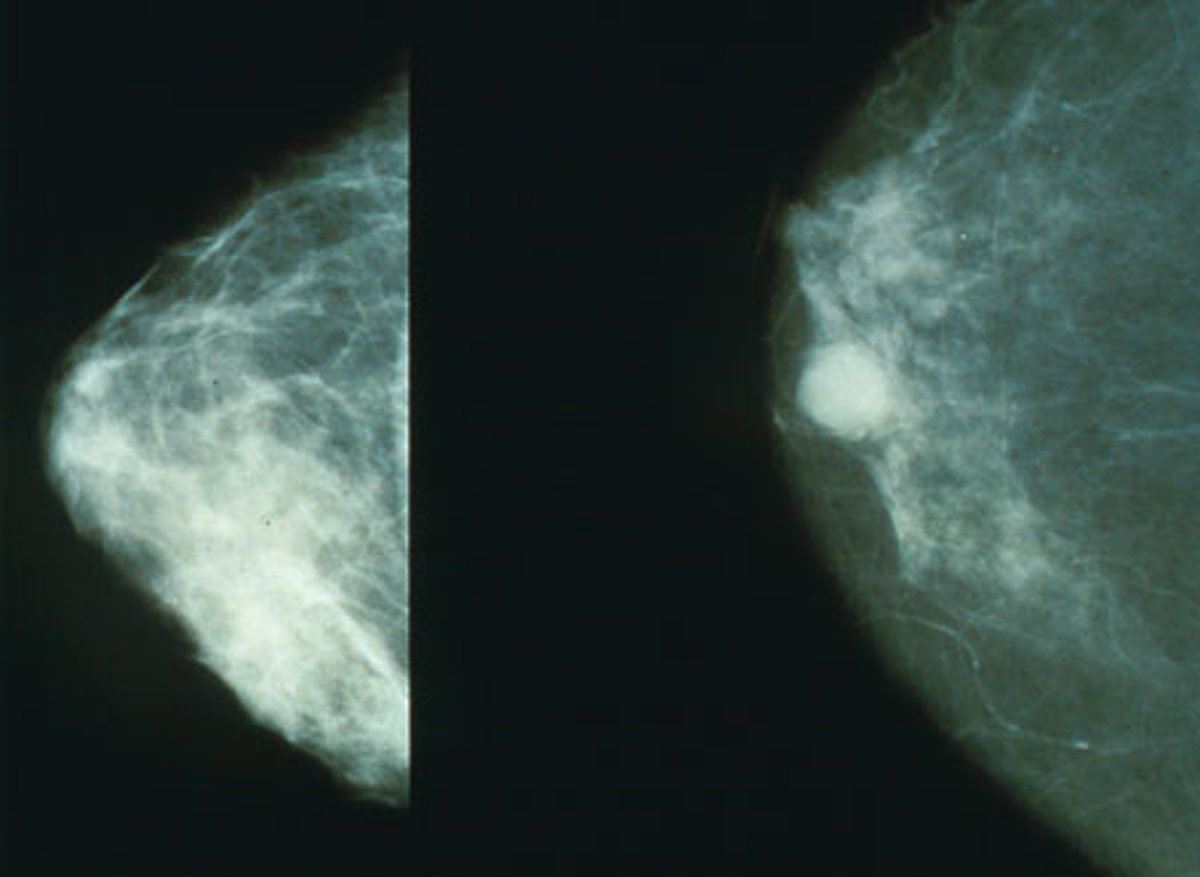

Los expertos recomiendan realizarse una mamografía anual a partir de los 40 años, ya que el diagnóstico precoz multiplica las posibilidades de curación. Además, las mamografías pueden detectar la mayoría de los cánceres de mama antes de que sean perceptible por palpación y de que provoquen los síntomas.